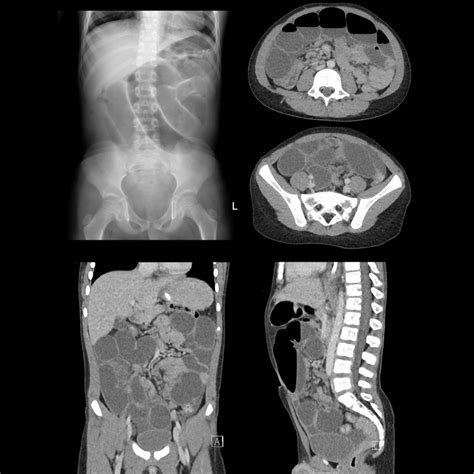

When a patient experiences unexplained gastrointestinal bleeding, especially in children, physicians often look for specific congenital anomalies. One of the most significant yet elusive causes of this issue is Meckel’s diverticulum. To identify this condition, medical professionals frequently rely on a specialized diagnostic tool known as a Meckel's Diverticulum Scan. This diagnostic procedure, formally referred to as a Meckel's scintigraphy, is a nuclear medicine imaging test designed to pinpoint the presence of ectopic gastric mucosa—stomach tissue that has grown in an abnormal location within the small intestine. By understanding how this scan works, what it detects, and how it is performed, patients and caregivers can better navigate the diagnostic process for unexplained digestive health concerns.

Meckel’s diverticulum is the most common congenital defect of the gastrointestinal tract, occurring in approximately 2% of the population. It is essentially a small pouch located on the wall of the lower part of the small intestine, present at birth. While many individuals live their entire lives without knowing they have it, others experience complications when the lining of this pouch contains cells similar to those found in the stomach.

Because these cells secrete acid, they can cause ulceration, bleeding, or perforation in the surrounding intestinal tissue. This often leads to painless, significant rectal bleeding, which is the primary reason doctors order a Meckel’s Diverticulum Scan. The scan is highly specific because it tracks the chemical uptake of these gastric cells, allowing for a non-invasive identification of the offending tissue.

A Meckel’s Diverticulum Scan utilizes a radioactive tracer, typically Technetium-99m pertechnetate. This tracer is absorbed by the gastric mucosa cells, making them visible under a specialized camera known as a gamma camera. The procedure is generally broken down into several stages to ensure the highest accuracy:

The interpretation of a Meckel’s Diverticulum Scan requires expertise in nuclear medicine. A positive result is indicated by a “hot spot”—an area of increased radioactivity that appears in the lower abdomen during the imaging sequence. This “hot spot” corresponds to the area where the technetium-99m has accumulated in the gastric mucosa.